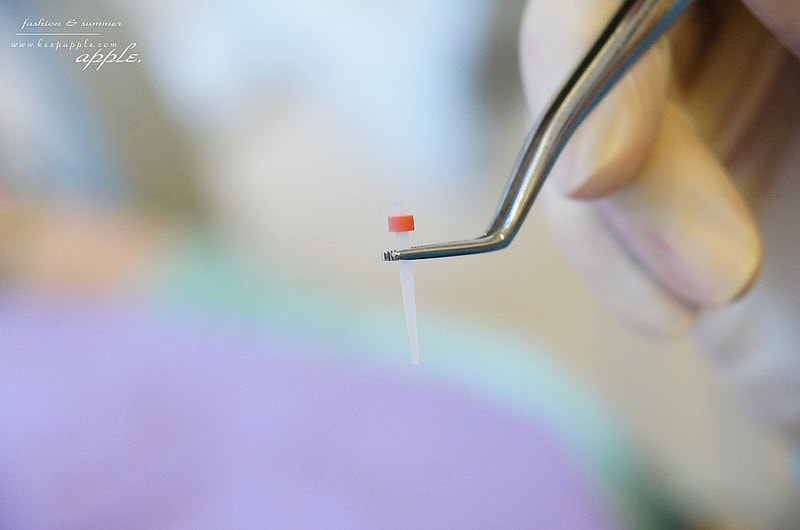

挖開之後把根心柱放進去

這可以向下分散咬合力量到牙根

向上支撐牙齒結構

然後再照光讓它融合